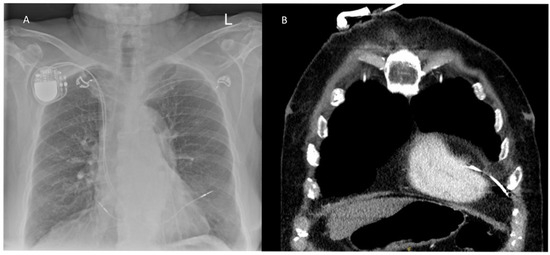

Background: Cardiac implantable electronic device (CIED) lead perforation is a rare but potentially catastrophic complication. As global device implantations increase, understanding the clinical spectrum and optimal management of this complication is essential. This study characterizes the clinical presentation, diagnostic strategies, and outcomes of lead perforation over a 25-year period. Methods: A retrospective analysis was conducted on 32 patients diagnosed with CIED lead perforation between 2000 and 2025 at a high-volume center. Perforations were classified by timing: acute (<24 h), subacute (1–30 days), and chronic (>30 days). Data included demographics, comorbidities, imaging modalities, and procedural interventions. Results: The mean patient age was 76.0 ± 11.7 years, with a mean body mass index (BMI) of 25.5 ± 3.4 kg/m2. Subacute presentation was the most frequent (59.3%, n = 19), followed by acute (28.1%, n = 9) and chronic (12.5%, n = 4) cases. The right ventricle was the primary site of perforation (90.6%). While chest X-rays served as an initial screening tool in 62.5% of cases, diagnosis relied on multimodal imaging, with Computed Tomography (CT) providing definitive confirmation in 31.3% of the cohort, particularly when lead parameters remained stable. Management was risk-stratified based on hemodynamic status. The majority of patients (71.9%, n = 23) underwent successful transvenous lead removal via simple traction. However, 25% (n = 8) presented with hemodynamic instability, and 21.9% (n = 7) suffered from cardiac tamponade. These high-risk cases required surgical intervention, including sternotomy (n = 4), thoracotomy (n = 2), or pericardiotomy (n = 3). Notably, 62.5% of hemodynamically unstable patients were on oral anticoagulants. All patients survived to discharge, with no in-hospital mortality. The median length of hospital stay was 3 days. Conclusions: CIED lead perforation often presents subacutely with subtle clinical signs. CT imaging has emerged as the gold standard for definitive diagnosis. While percutaneous transvenous removal is safe and effective for stable patients, immediate surgical backup is vital, as patients—particularly those on anticoagulation—can deteriorate rapidly. Full article

Figure 1